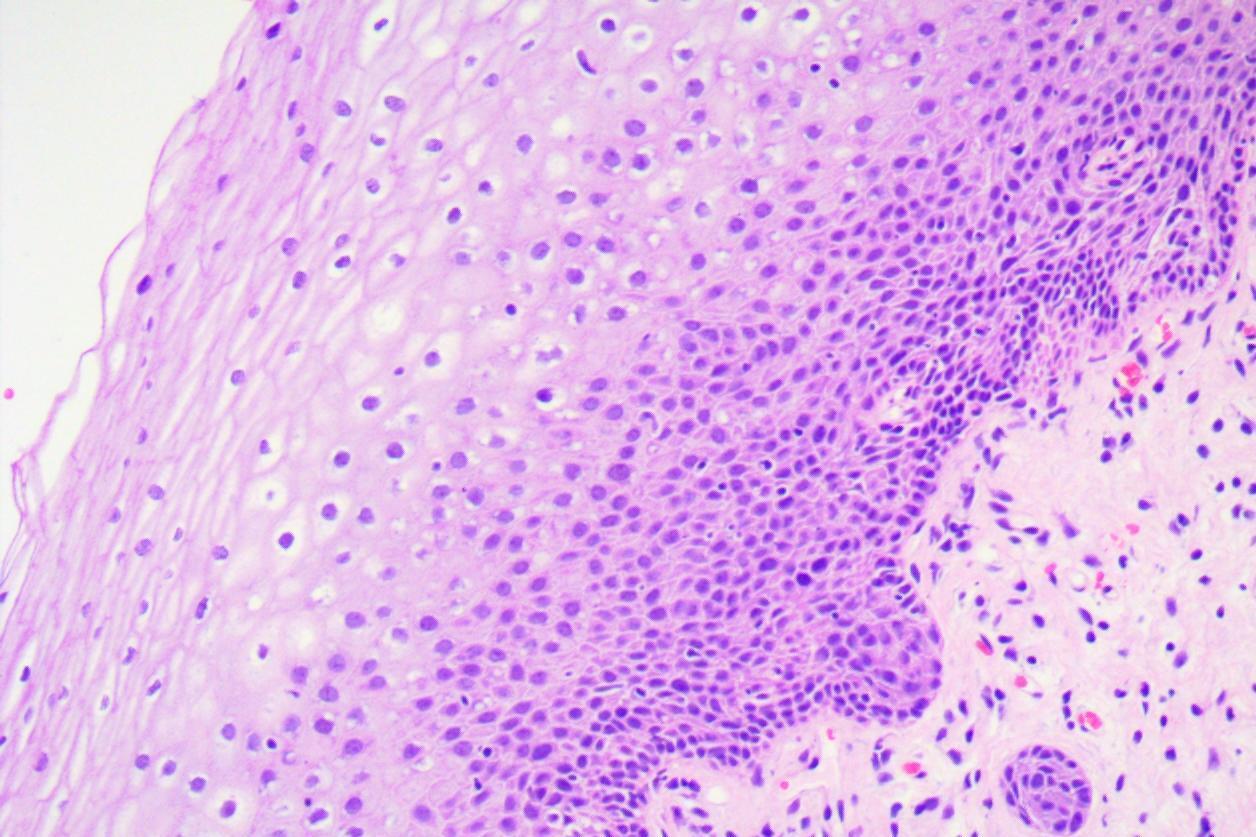

Hpv16